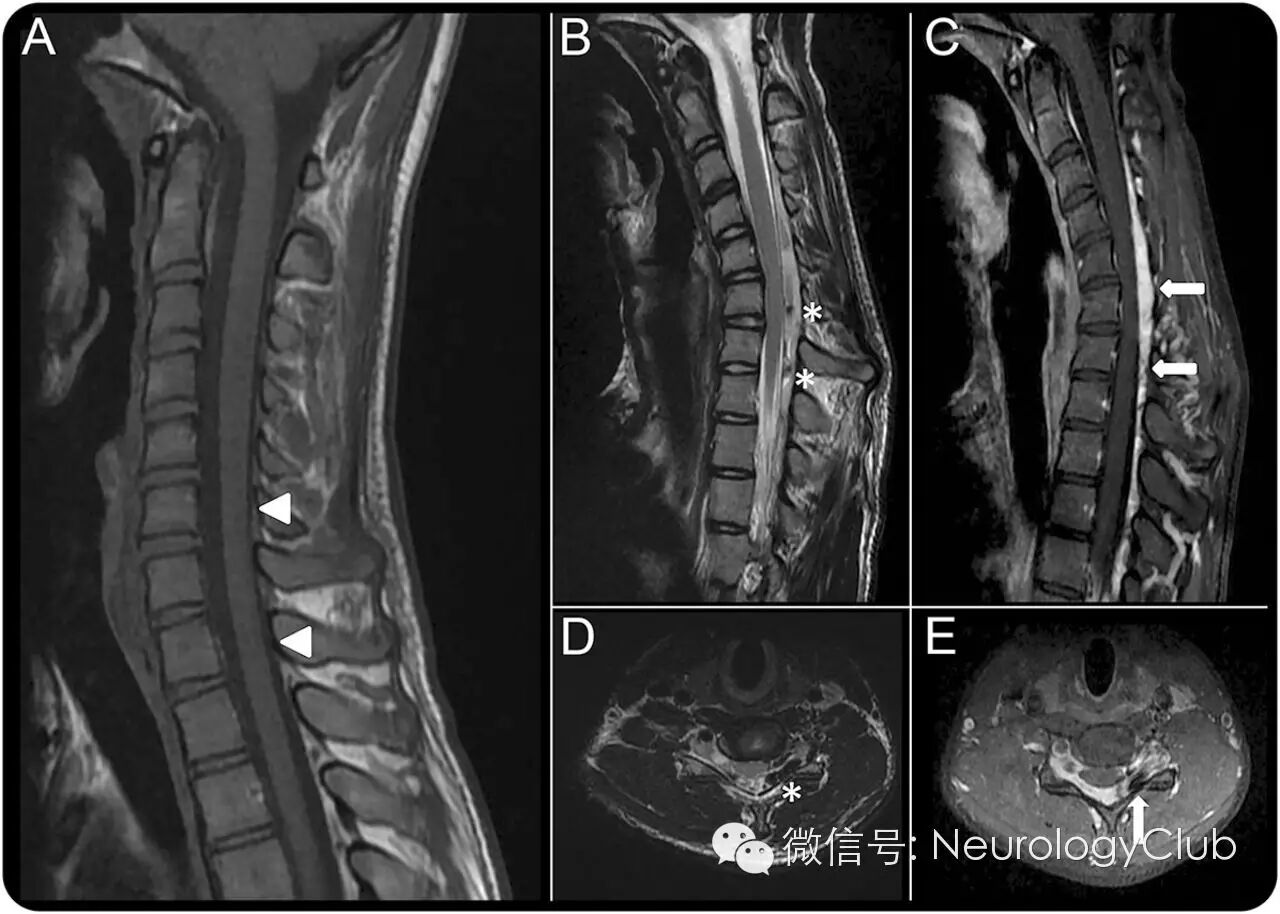

(图2:A:非屈位T1WI提示C7-T1脊髓萎缩;B、D:屈颈位T2WI提示硬膜后腔前移伴颈髓受压;C、E:硬膜外静脉丛充血强化)